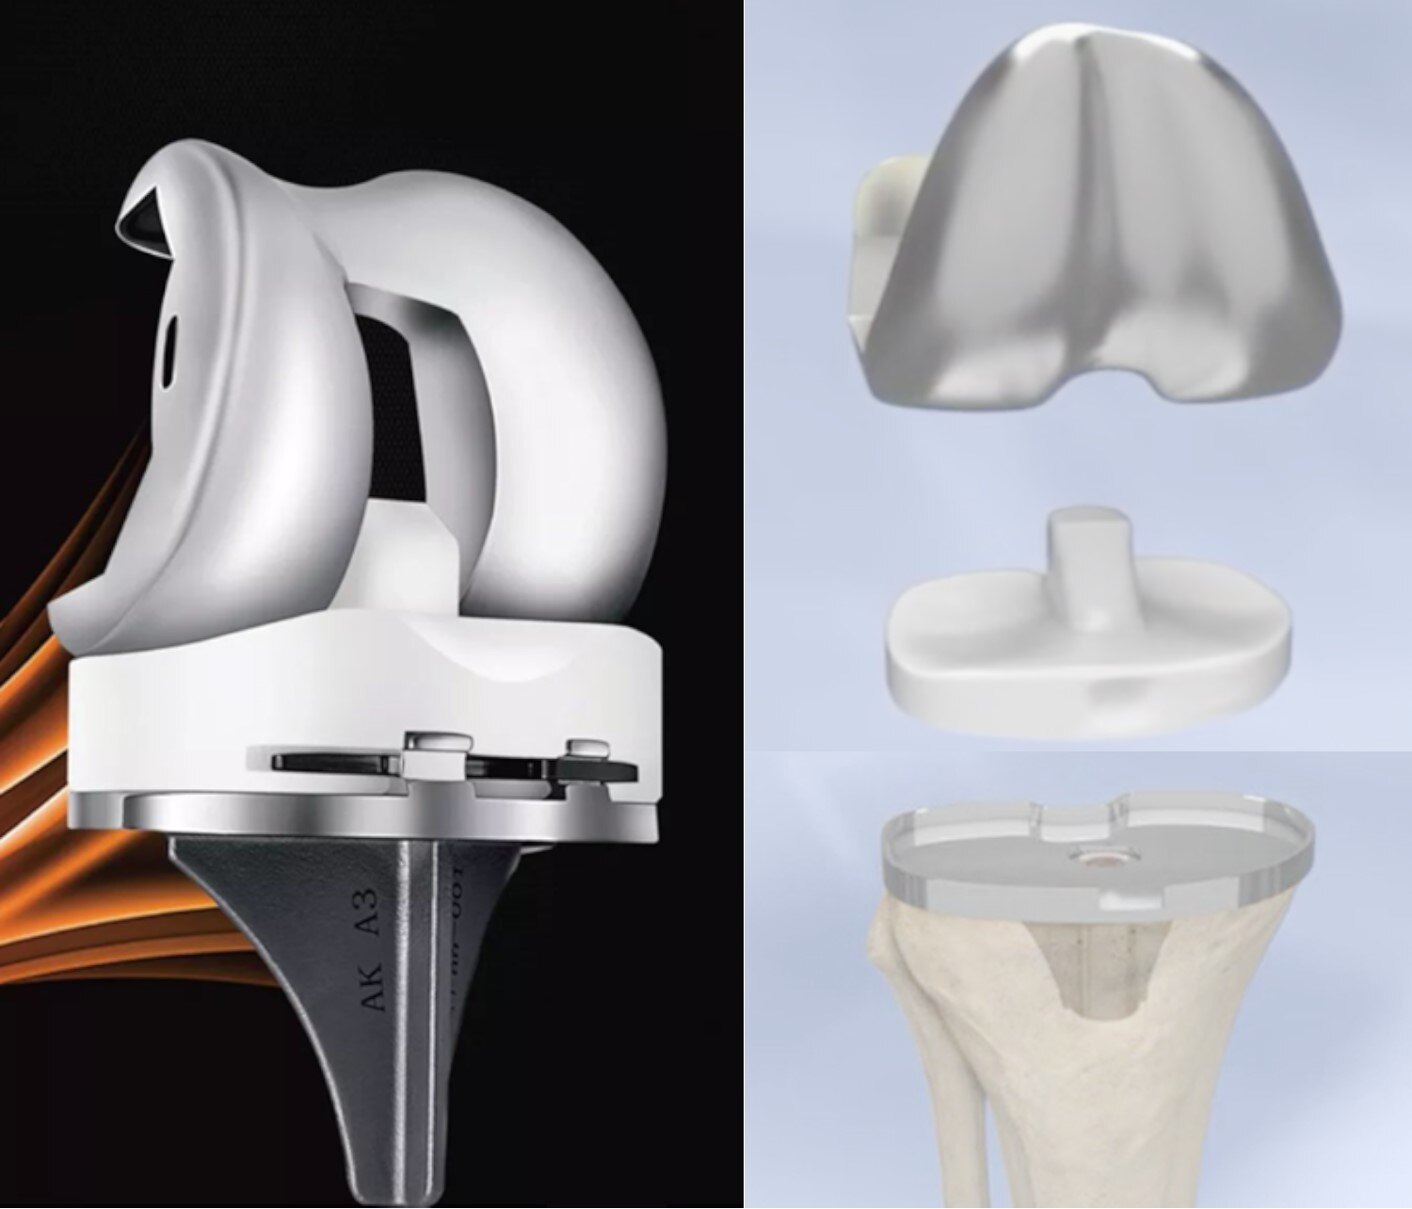

今天跟大家分享一下人工全膝表面置换(Total Knee Arthroplasty, TKA)。经过50余年的发展,人工全膝表面置换已经成为一项成熟的手术技术,采用耐磨的人工材料(金属/陶瓷和聚乙烯,图2)来替换磨损或破坏的关节表面(图3),从而缓解关节疼痛、恢复关节屈伸和负重行走活动,帮助病友们重新获得健康的生活。

图2. 常规的人工膝关节设计,包括分别镶嵌在股骨侧表面和胫骨侧表面的股骨髁假体和胫骨平台假体、中间的